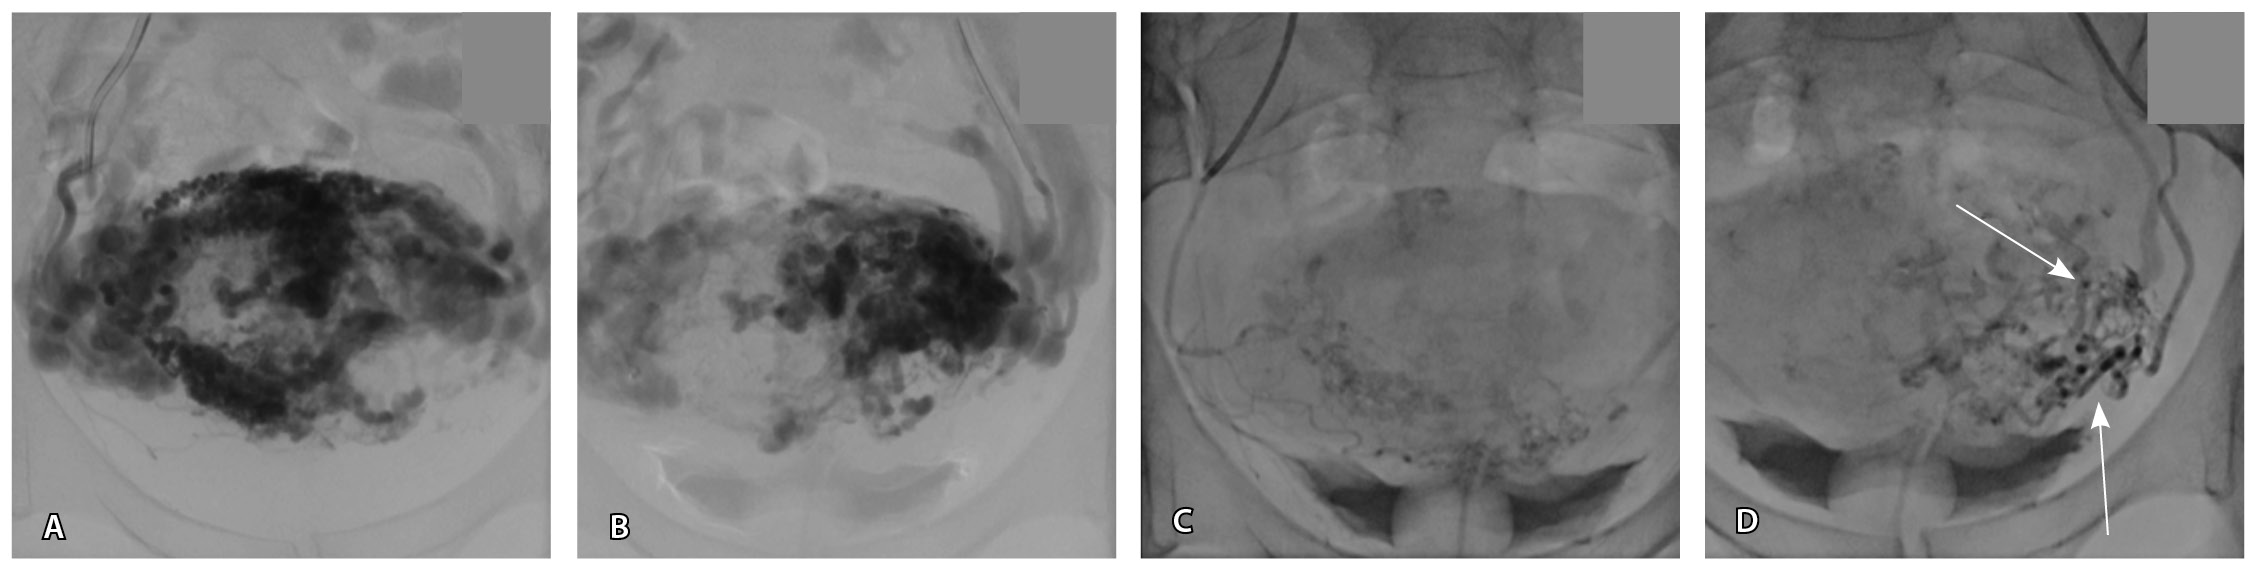

По наружной поверхности нижнего маточного сегмента и в параметрии определяется наличие полнокровной сосудистой сети с артериовенозными анастомозами. При контрастировании визуализируются фрагментарные участки гиперваскулярного накопления контраста вышеописанным образованием в рубцовой нише, а также определяется наличие артериовенозной сосудистой мальформации (рис. 2).

Рис. 2. Магнитно-резонансная томограмма, динамическое контрастное усиление в режиме Т1-взвешенного изображения FS. До контраста (А), в раннюю артериальную фазу (Б), паренхиматозную фазу (В), выделительную фазу (Г) определяются многочисленные патологические сосуды, зоны неоангиогенеза, сосудистые шунты как в стенке матки, так и в параметрии по типу артериовенозной мальформации

Для детализации сосудистого компонента артериовенозной мальформации, в том числе с целью планирования дальнейшей лечебной тактики, пациентке выполнено КТ-исследование (рис. 3). Обнаружено: тело матки увеличено, определяется образование в полости матки неясного генеза. В стенках матки сосудистая артериальная сеть с ранним сбросом контрастного вещества во внутреннюю подвздошную вену с двух сторон (диаметром 0,7 см справа, 0,8 см – слева), правую яичниковую вену (диаметром до 1,2 см), левую яичниковую вену (диаметром до 0,6 см).

Рис. 3. Компьютерная томограмма органов таза с контрастированием. Тело матки увеличено, в стенках матки сосудистая артериальная сеть (стрелки) с ранним сбросом контрастного вещества во внутреннюю подвздошную вену с двух сторон, правую и левую яичниковые вены (стрелка)